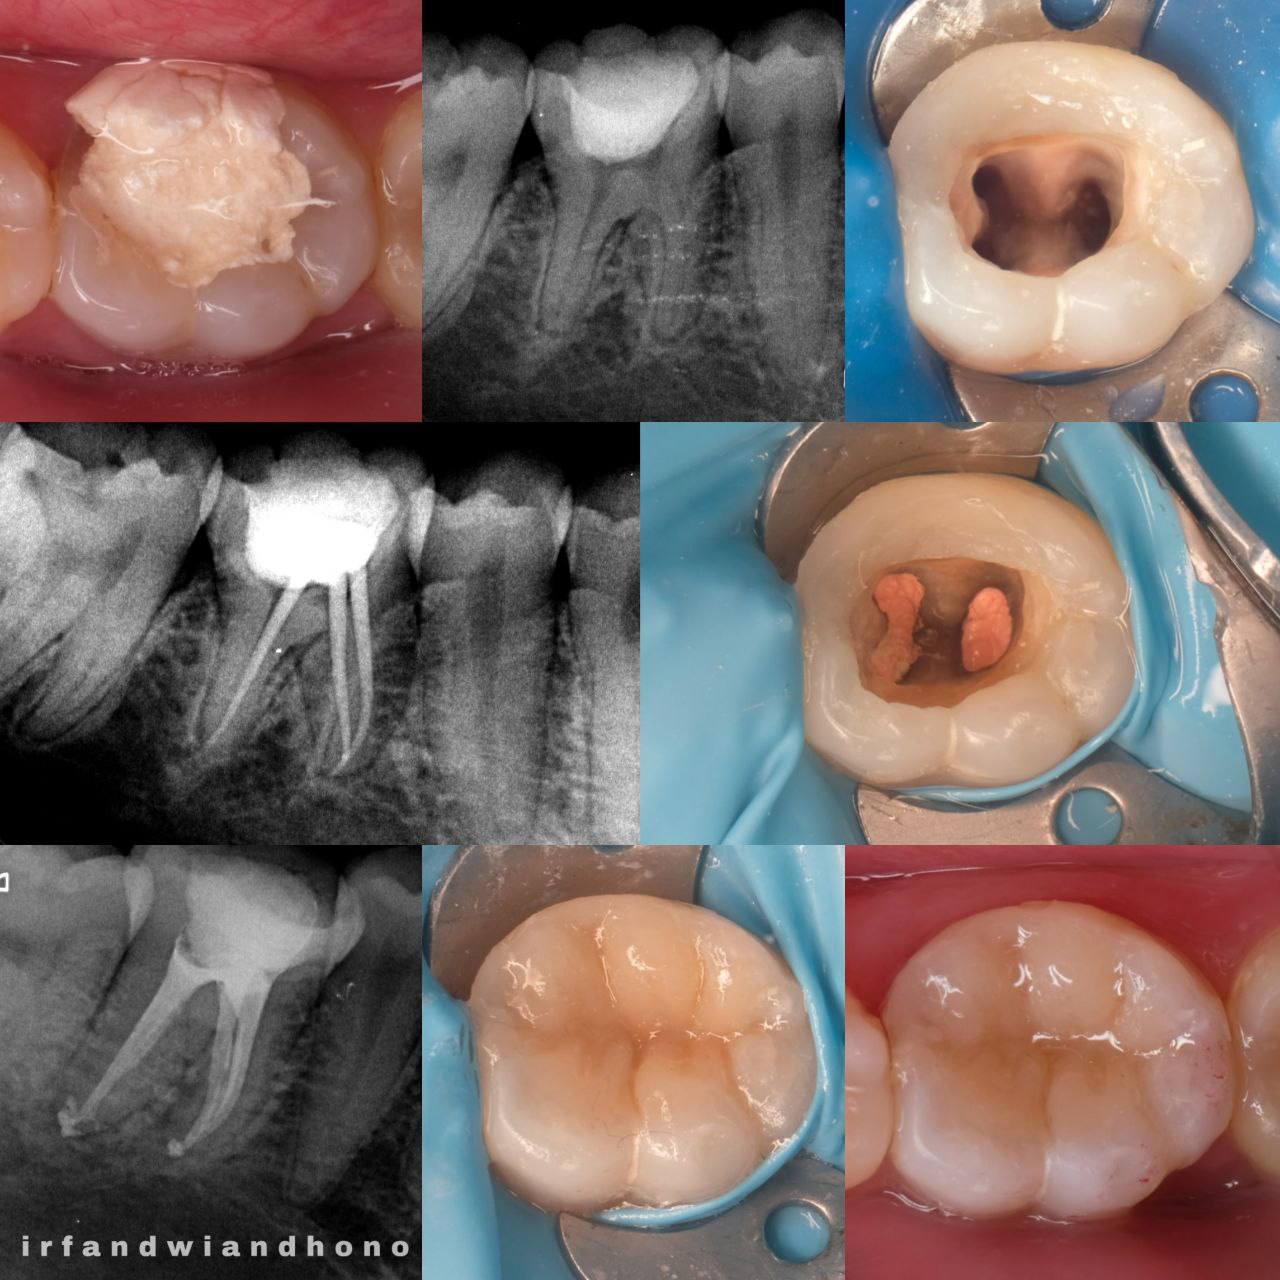

Spesialis Konservasi Gigi adalah cabang spesialistik kedokteran gigi yang mengatasi kelainan jaringan keras gigi, pulpa, periapikal, dengan cara melakukan perawatan gigi untuk mengembalikan fungsi stomatognatik, estetik, dan mempertahankan gigi selama mungkin di dalam rongga mulut

Prosedur untuk mengobati infeksi atau kerusakan pada pulpa gigi dengan membersihkan, mendisinfeksi, dan menutup saluran akar untuk menyelamatkan gigi dari pencabutan.